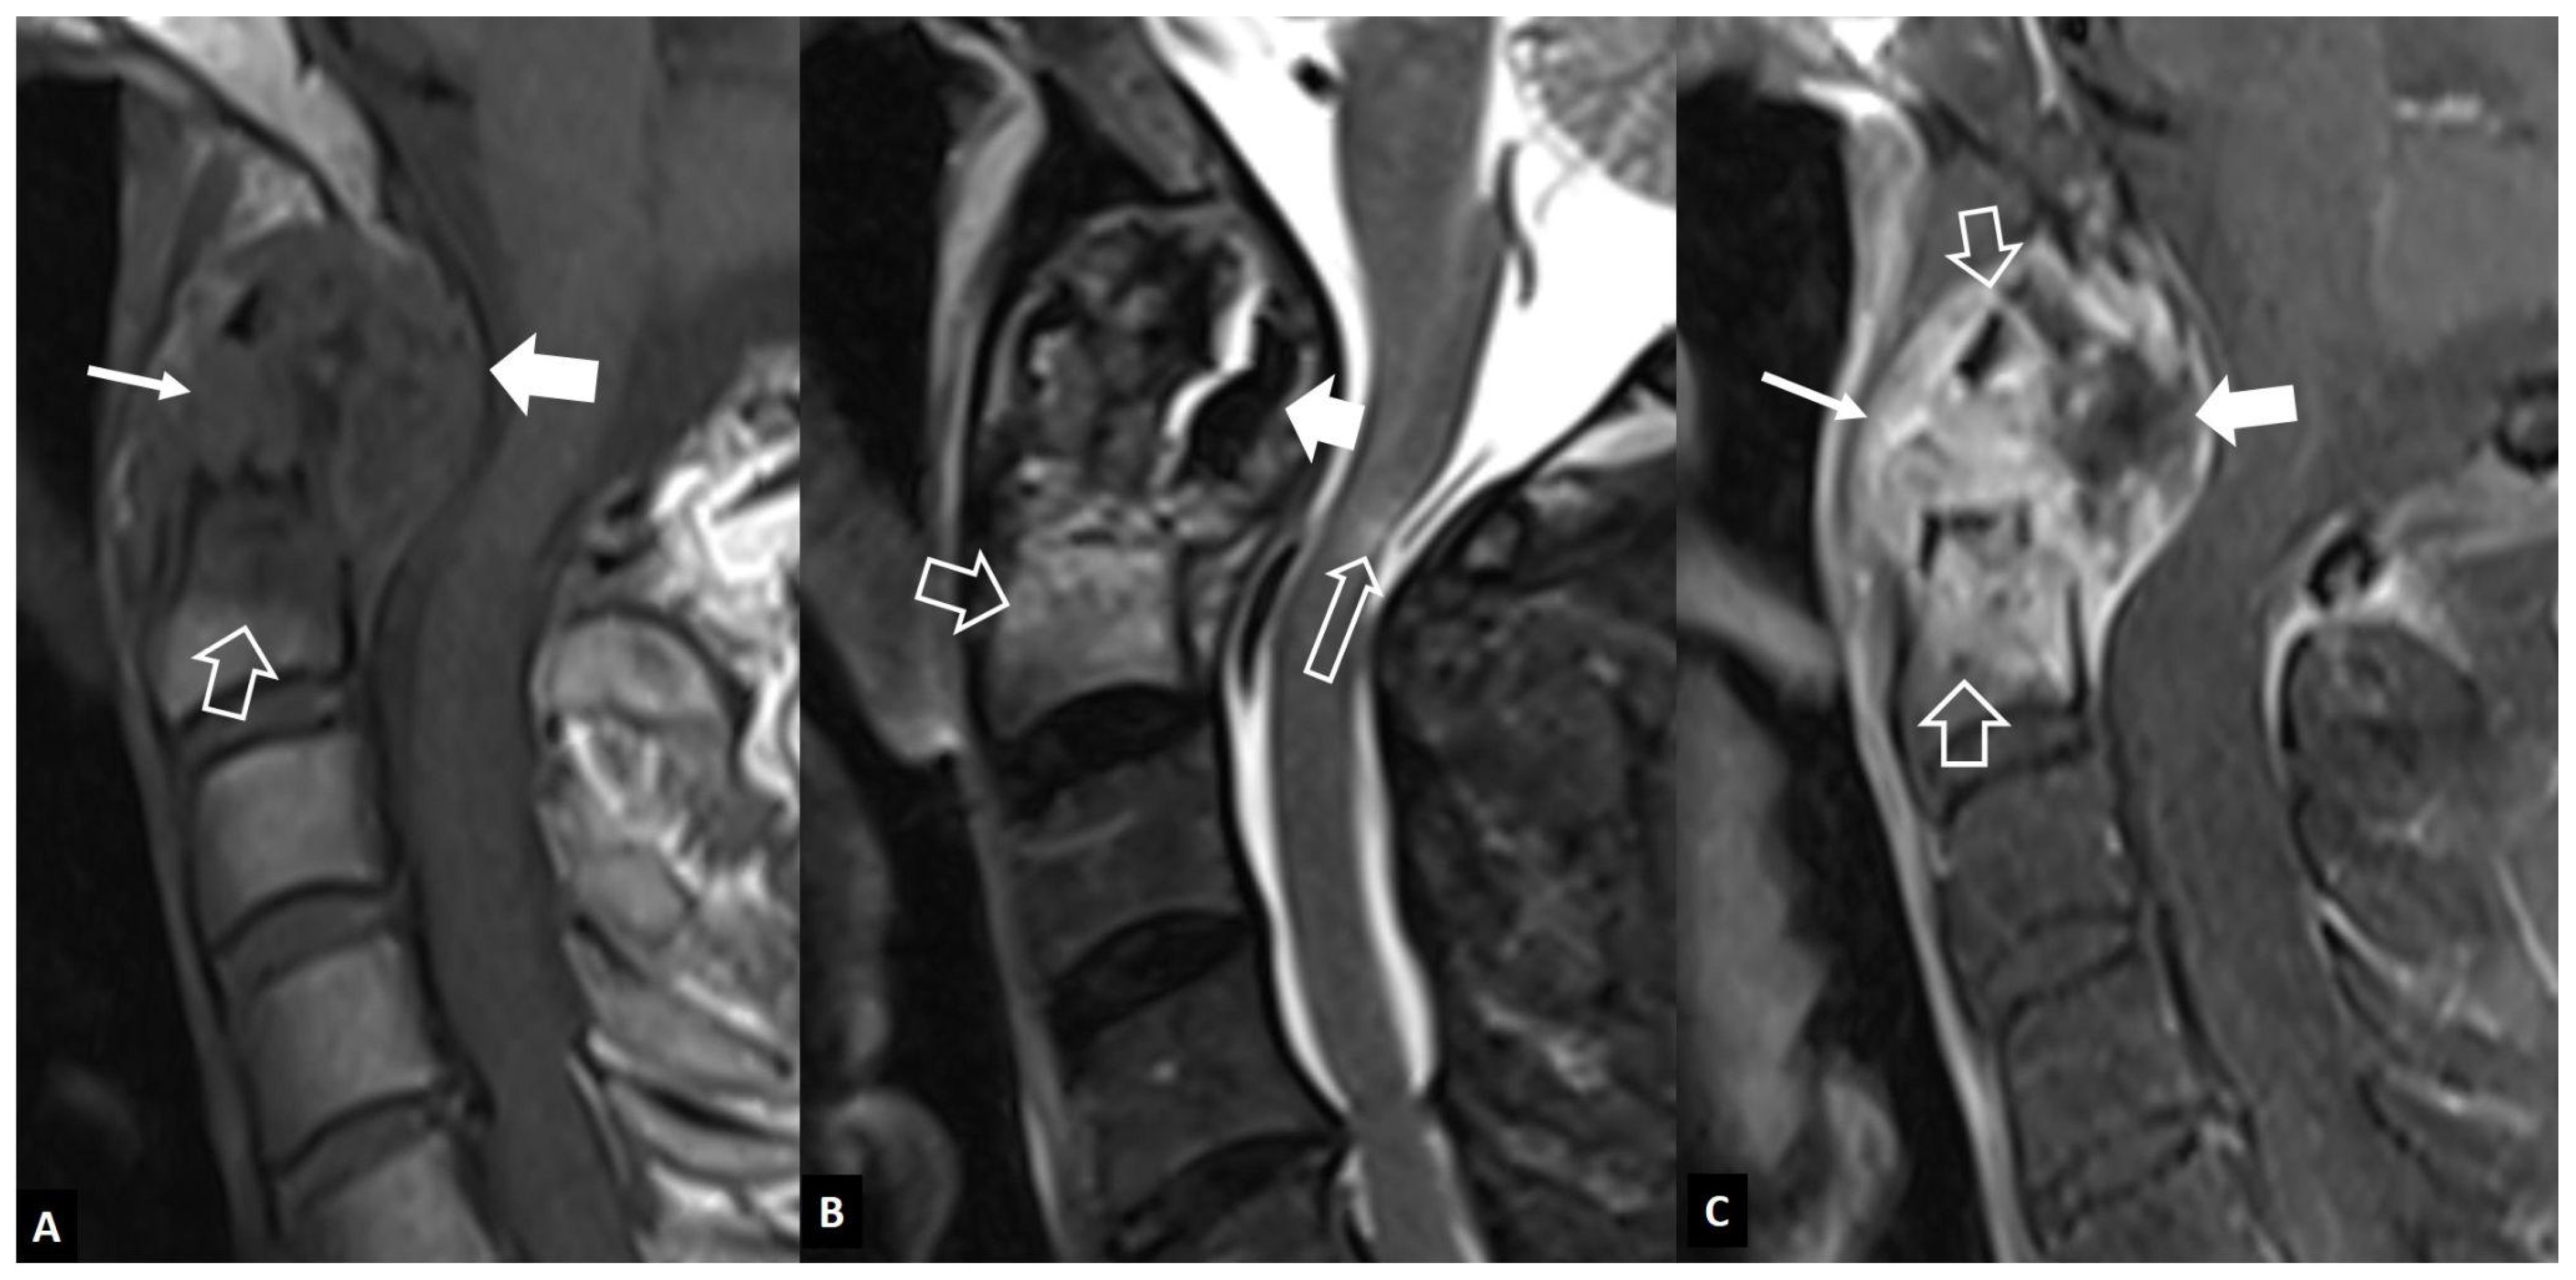

2.1.3. SAPHO Syndrome

2.1.4. Destructive Spondyloarthropathy